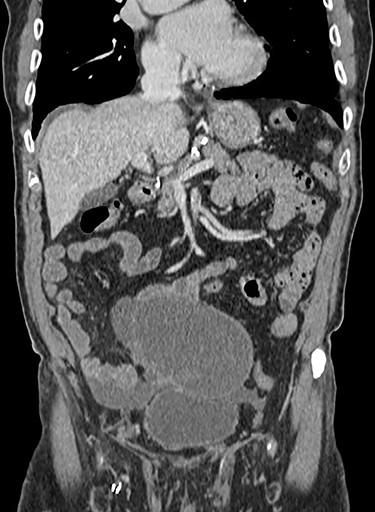

Cross sectional computed tomography imaging of the abdomen and pelvis with contrast confirmed a large cystic lesion within the lower abdomen as shown in Fig. 1. This case was discussed in the colorectal multidisciplinary team meeting where the possibility of the mass being an AMN was raised. It was radiologically thought to be unlikely and a provisional diagnosis of a mesenteric cyst was made.

Cross sectional computed tomography image showing a large cystic, trabeculated lesion with an enhancing wall in the lower abdomen measuring 11.3 × 11.5 × 16 cm.